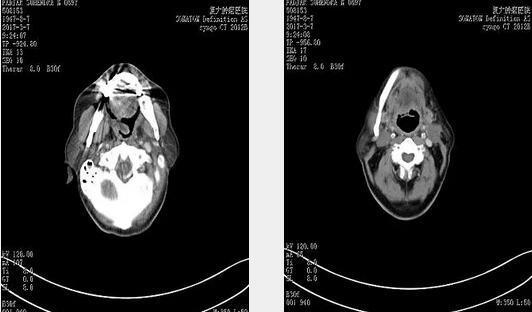

2016年11月5日治療前CT 顯示左側扁桃體鱗癌,腫瘤侵犯舌根及會厭,口嚥腔狹窄。

2017年3月7日2次消融後CT,左側扁桃體腫瘤明顯退縮。

2017年7月4日頸部淋巴結清掃術後CT,原雙側頸部轉移性病變,已消失。